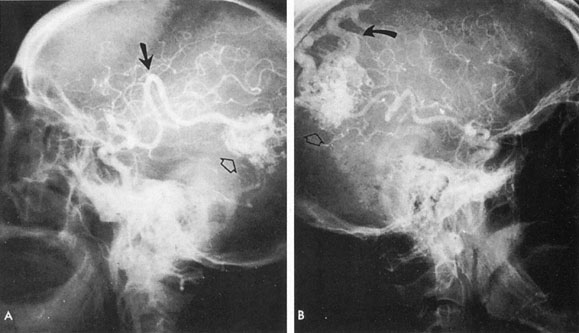

From 85% to 90% of AVMs are in the supratentorial compartment and are supplied primarily by the carotid circulation (Figs. 7 and 8). The remainder are supplied by the vertebrobasilar system. The approximate frequency of location is as follows: frontal, 22%; temporal, 18%; parietal, 27%; occipital, 5%; and deep intraventricular or paraventricular, 18%. The intracerebral site of the malformation does not necessarily indicate that there will be signs referable to that area simply from the mass effect of the malformation. Clinical features primarily result from subarachnoid hemorrhage or intraparenchymal hemorrhage with hematoma formation.

Fig. 7. Supratentorial arteriovenous malformation in a 28-year-old woman with a history of focal motor seizures for many years and a recent subarachnoid hemorrhage. A: Lateral projection carotid arteriogram demonstrating a huge deep hemispheral arteriovenous malformation. B: Frontal projection. C: Fundus photograph showing anomalous tortuous vasculature in each eye. No retinal arteriovenous shunt was detectable.

Fig. 8. Multiple supratentorial arteriovenous malformations (AVMs). A: Lateral projection of left carotid arteriogram shows dilated afferent artery (solid arrow) feeding the right hemispheric parietal AVM (open arrow). B: Right carotid injection fills a second, more posteriorly located, parietooccipital AVM (open arrow), which drains immediately to markedly dilated cortical veins (curved arrow).

In general, when hemorrhage occurs involving a portion of the visual radiations, a homonymous visual field defect is to be expected. Selective involvement of the anterior visual pathways may occur either with extensive venous angiomas at the base of the brain or as part of the Wyburn-Mason syndrome (see later), with direct involvement of the optic nerve, chiasm, or tract. Other variants such as congenital cavernous hemangiomas may involve the anterior visual pathways,68 as may intraparenchymal cryptic AVMs69 and present as symptomatic visual loss also resulting from hemorrhage and hematoma. Amaurosis fugax may even be the presenting symptom of supratentorial AVMs when blood is shunted to the meningeal circulation from the ophthalmic artery.70 When supratentorial AVMs drain into dural venous sinuses or the vein of Galen, distant ocular effects evolve, such as proptosis71 or ophthalmoplegia72 because of arterialization of cavernous sinus complex.

Of particular interest are those AVMs that involve the occipital lobe (Fig. 9). The clinical differentiation of migraine from a cerebral AVM was previously regarded as difficult because the clinical features of occipital lobe AVMs include visual phenomena or headaches. However, in most cases the clinical distinction is possible. In 26 cases with occipital AVM, two distinct syndromes were defined in 18 patients: occipital epilepsy and occipital apoplexy.73 Focal seizures with occipital malformations consist of elementary visual sensations similar to the phenomena evoked by direct cortical stimulations. When seizure activity occurs in the striate cortex (area 17), the patient usually reports sensations of moving lights in the right or left homonymous fields. The sensations are poorly formed, episodic, usually brief, sometimes colored, and unassociated with the angular, scintillating figures so characteristic of migrainous cortical phenomena. Epileptic discharges from areas 18 and 19 cause photopsias that are unlikely to remain stationary and to flicker rapidly. The epileptic photopsias usually last only seconds; occasionally they last for a few minutes before the onset of a generalized seizure. In other instances only the brief visual episodes occur without spreading to produce a generalized seizure. Momentary dimming or blindness in one or both homonymous fields may be experienced with seizure activity in the occipital areas.

Fig. 9. Carotid arteriogram of an occipital lobe arteriovenous malformation (AVM). Lateral (A) and frontal (B) projections demonstrating a small occipital AVM (arrow). The patient was a 23-year-old woman who presented with severe apoplectic unilateral headache, total left homonymous hemianopia, and mild nuchal rigidity. Despite xanthochromic cerebrospinal fluid, she was initially diagnosed elsewhere as having migraine. An AVM was successfully resected, and a small occipital lobe hematoma was removed.

The detection of intracranial AVMs is facilitated by CT scanning and MRI (Fig. 10),88 but optimal management requires selective angiography89 that assesses the size and configuration of the mass, the number and location of feeding arteries, the flow characteristics and degree of steal from brain parenchyma, and the pattern of venous drainage.

Fig. 10. Neuroimaging of arteriovenous malformation. A: Coronal magnetic resonance imaging (MRI) (TR, 600 ms; TE, 20 ms) shows wedge-shaped vascular mass extending from the surface of the parietal cortex (white arrows) to the lateral ventricle (black arrows; asterisk, arterial feeder). B: Posteroanterior left arteriogram of the same lesion. C: Axial computed tomography scan with contrast enhancement. D: Axial MRI of a large arteriovenous malformation, first echo (TR, 2000 ms; TE, 20 ms). E: Second echo (TR, 2000 ms; TE, 90 ms). (From Smith HJ, Strother CM, Kikuchi Y, et al: MR imaging in the management of supratentorial intracranial AVMS. AJNR Am J Neuroradiol 9:225, 1988.)